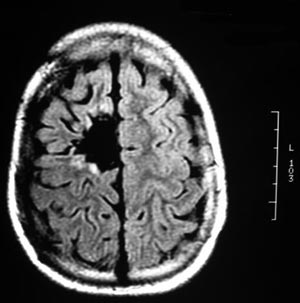

Figura 92 - Ressonância nuclear magnética de encéfalo mostrando a lesão junto à área motora no hemisfério cerebral direito.

Figura 96 - Ressonância nuclear magnética de encéfalo antes da cirurgia revelando a cavidade da cirurgia prévia